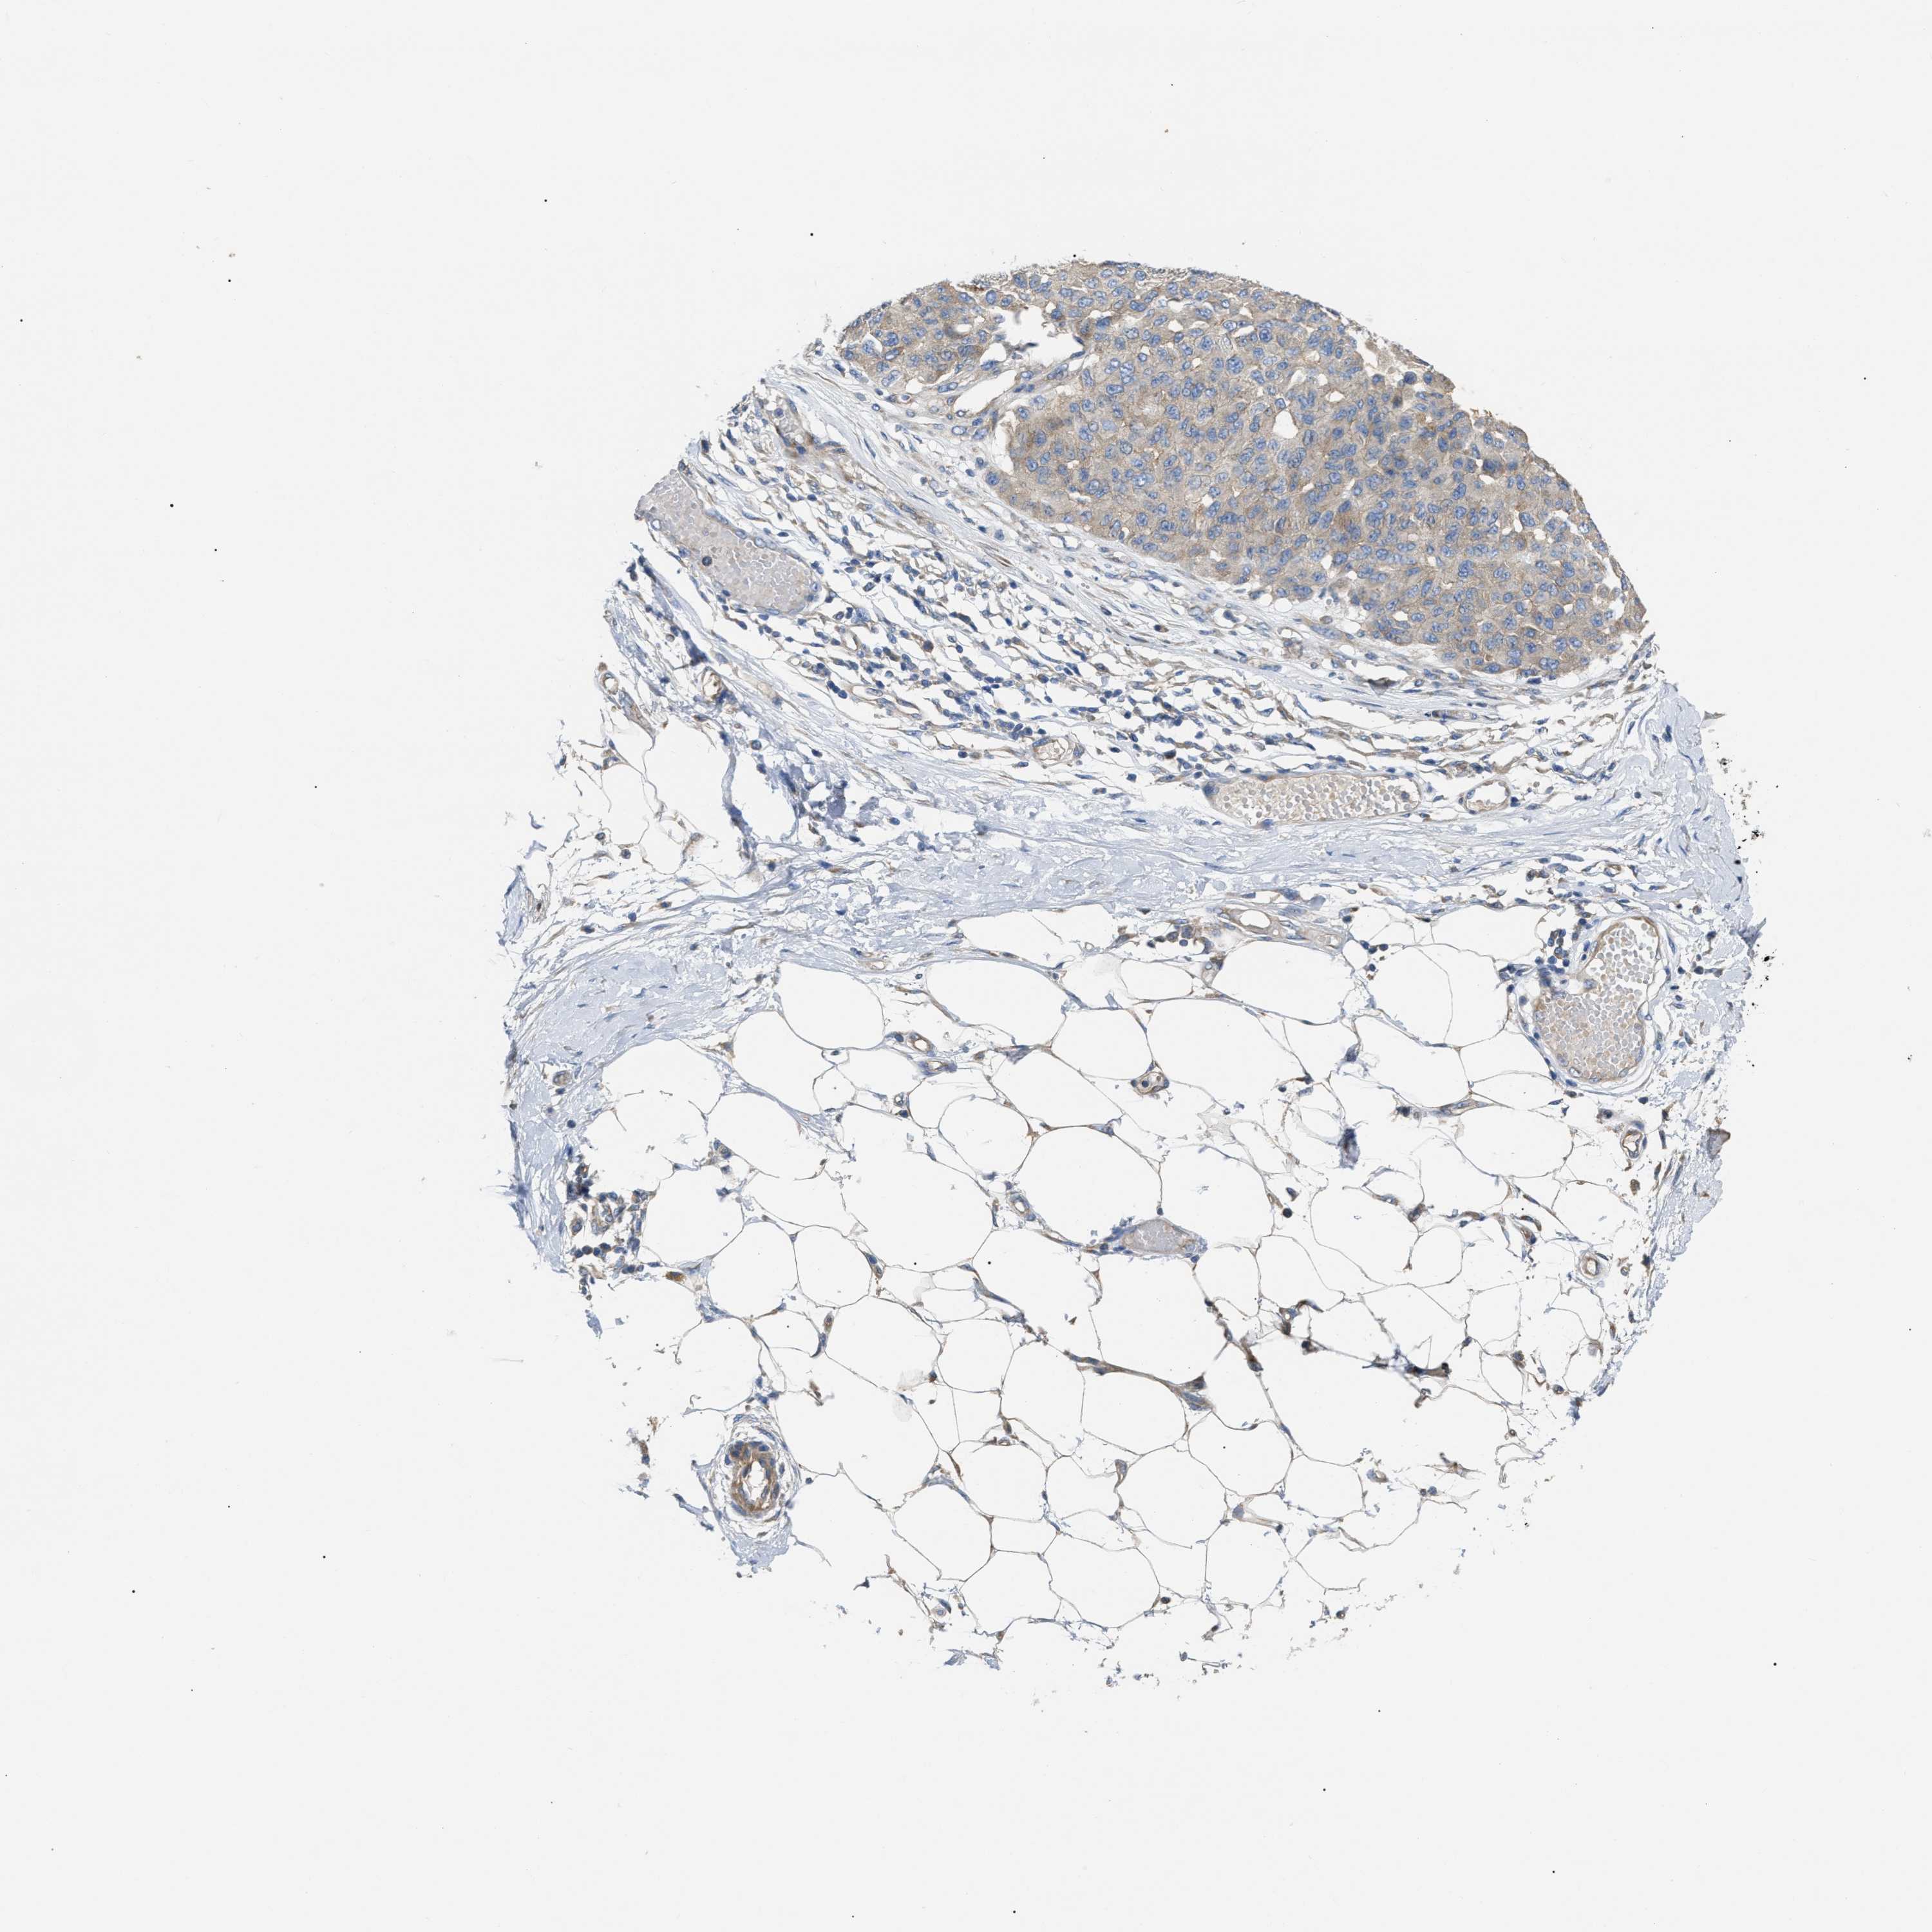

MELANOMA - Protein expressioni

A mouse-over function shows sample information and annotation data. Click on an image to view it in a full screen mode. Samples can be filtered based on level of antibody staining by selecting one or several of the following categories: high, medium, low and not detected. The assay and annotation is described here.

Note that samples used for immunohistochemistry by the Human Protein Atlas do not correspond to samples in the TCGA dataset.

Antibody stainingi

Antibody staining in the annotated cell types in the current human tissue is reported as not detected, low, medium, or high, based on conventional immunohistochemistry profiling in selected tissues. This score is based on the combination of the staining intensity and fraction of stained cells.

Each image is clickable and will lead to virtual microscopy that enables deeper exploration of all samples and also displays staining intensity scores, fraction scores and subcellular localization as well as patient and tissue information for each sample.

Antibody HPA018670

Antibody HPA019570

Staining

High

Medium

Low

Not detected

Intensity

Strong

Moderate

Weak

Negative

Quantity

>75%

75%-25%

<25%

None

Location

Nuclear

Cytoplasmic/membranous

Cytoplasmic/membranous,nuclear

Malignant melanoma, NOS

Malignant melanoma, Metastatic site